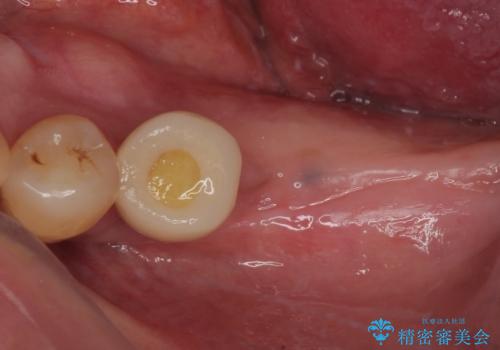

- 連結されている奥歯がグラグラしていて、インプラント治療を希望して来院された患者様です。

連結の手前の歯は歯根が破折して、クラウンが歯から外れており、奥の歯は動揺により歯根周辺の骨が吸収している状態でした。

骨吸収が甚大な後方は3ヶ月ほど待機して、手前は抜歯即時埋入により、短期間インプラント補綴治療を行うこととしました。

なお、後方の歯は痛みが酷かったため、初診時に抜歯をすることとなりました。